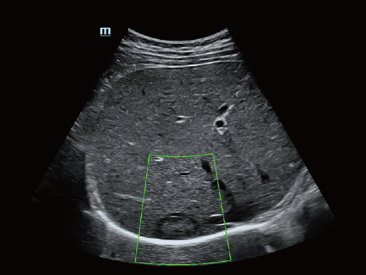

Mindray? ??? ??? ?? ??? ???? ??? ?? ??? ??? ????? ??? ????. ?? ???? ZONE Sonography? ??? ???? ?? Resona 7? ??? ZST+ ???? ?? ?? ? ?? ??? ????? ?? ??? ??? ??? ? ?? ????.

?? Resona 7? ???? ??? ?? ???? ??? ??? ???? ??? ?? ???? V Flow? ?? CNS ??? ?? 3D ??? ???? ?? ???? ?? ??? ?? ?? ?? ??? ??????. ???? ??? ??? ?? ?? ??? ??? ?? ?? ??? ??? Resona 7? ??? ???? ???? ??? ??? ??? ????.